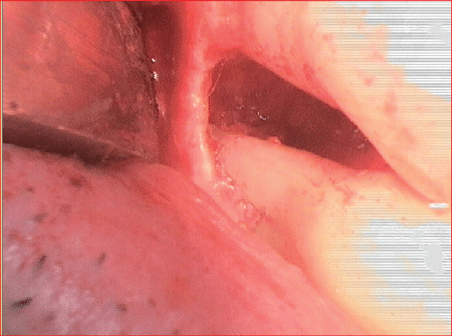

24和25牙周围的增强材料和增强区域被可吸收胶原膜覆盖(CopiOs心包膜,Zimmer Dental GmbH, Munich),并用Titan Pins固定(usstomed)(图14和15)。

图14:用可吸收膜覆盖骨块和垂直缺损。

图15:用可吸收膜覆盖骨块和垂直缺损。